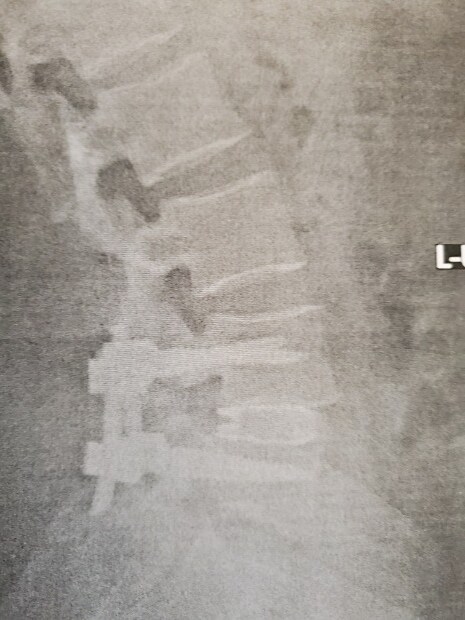

As many of you know, I am having back surgery in a few weeks (Nov 4th), I will have my L4 and L5 fused due to a birth defect.